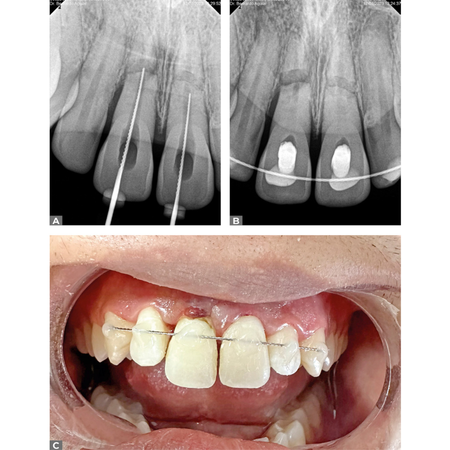

Conservative management of traumatic root fractures in upper central incisors: case report with two years of follow-up

INTRODUCTION: Dental trauma can result in various complicatioINTRODUCTION: Dental trauma can result in various complications, especially when not treated properly. Calcium hydroxide is widely used as an intracanal medication due to its b...